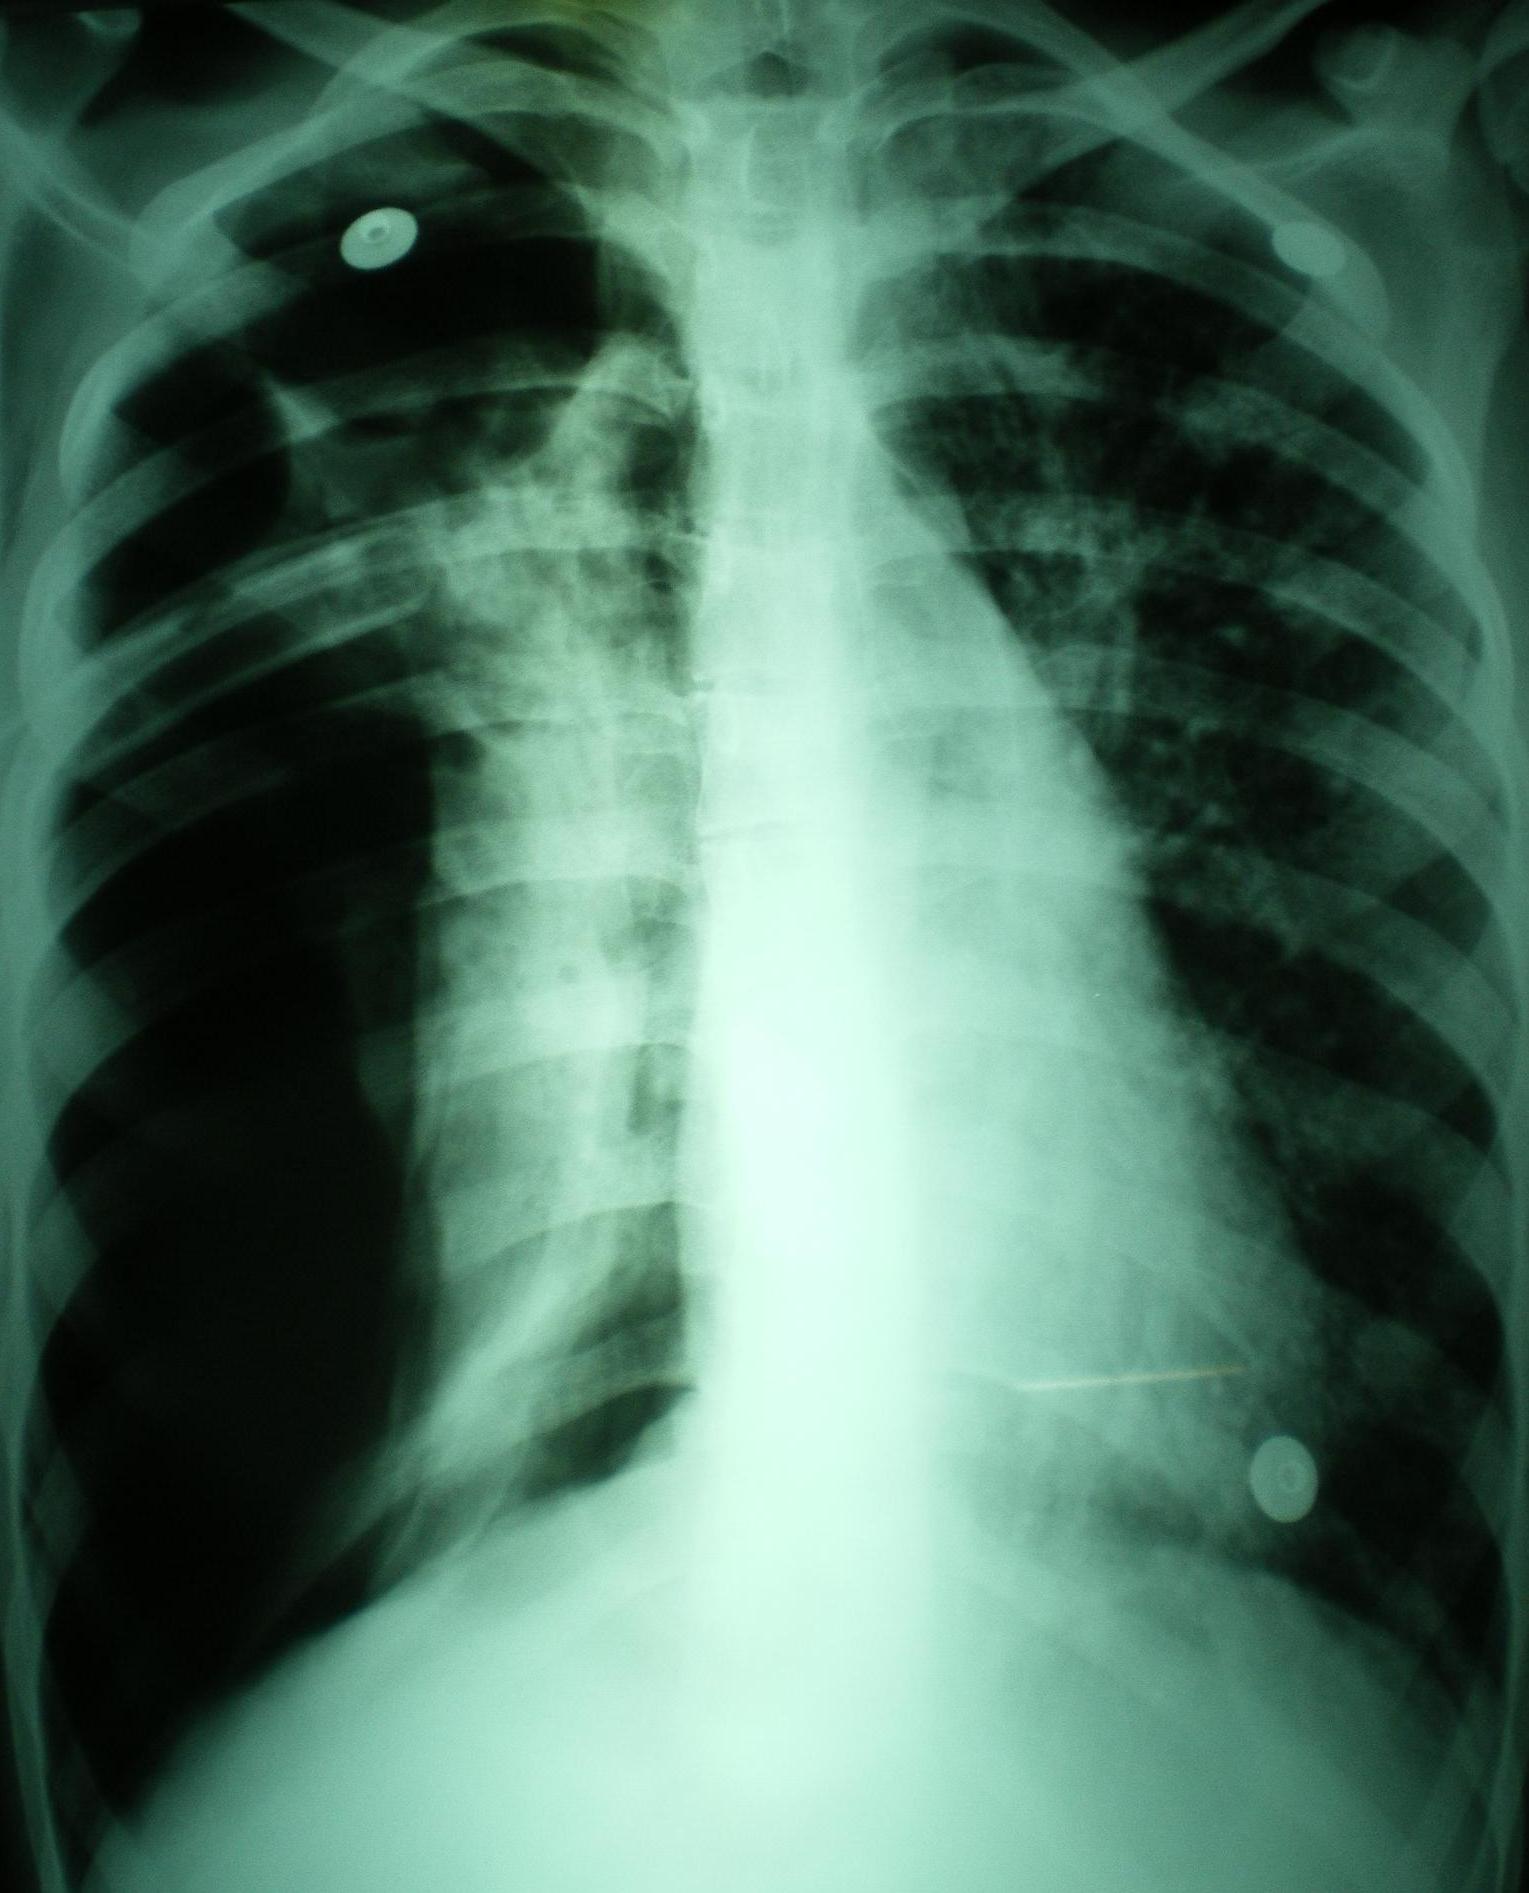

El edema pulmonar post-reexpansión puede producirse luego del tratamiento de grandes derrames pleurales, neumotórax o de atelectasias obstructivas. Se relaciona a la acción de mediadores inflamatorios que aumentan la permeabilidad vascular con exudación a los alvéolos. Comienza inmeditamente despues de la reexpansión y cede a los 5 a 7 dias; puede unilateral, bilateral o limitado a un único lóbulo. Los factores de riesgo son edad < 40 años, larga duración del colapso pulmonar (> 4 días), derrames pleurales > 1500 cc, neumotórax grado 3, rápida reexpansión, y aplicación de presión negativa intrapleural. El tratamiento es de soporte, pero lo mas importante es la prevención reconociendo los factores de riesgo para su desarrollo ya que tiene una mortalidad superior al 20%.